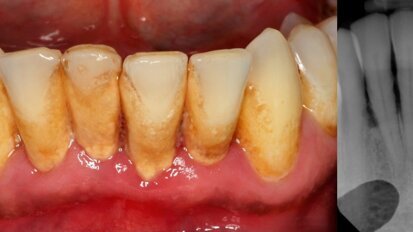

Family characteristics affect the periodontal diseases in children and adolescents

BRISBANE, Australia: We have enough literature to demonstrate an association between dental caries and family characteristics. However, the same is not ...